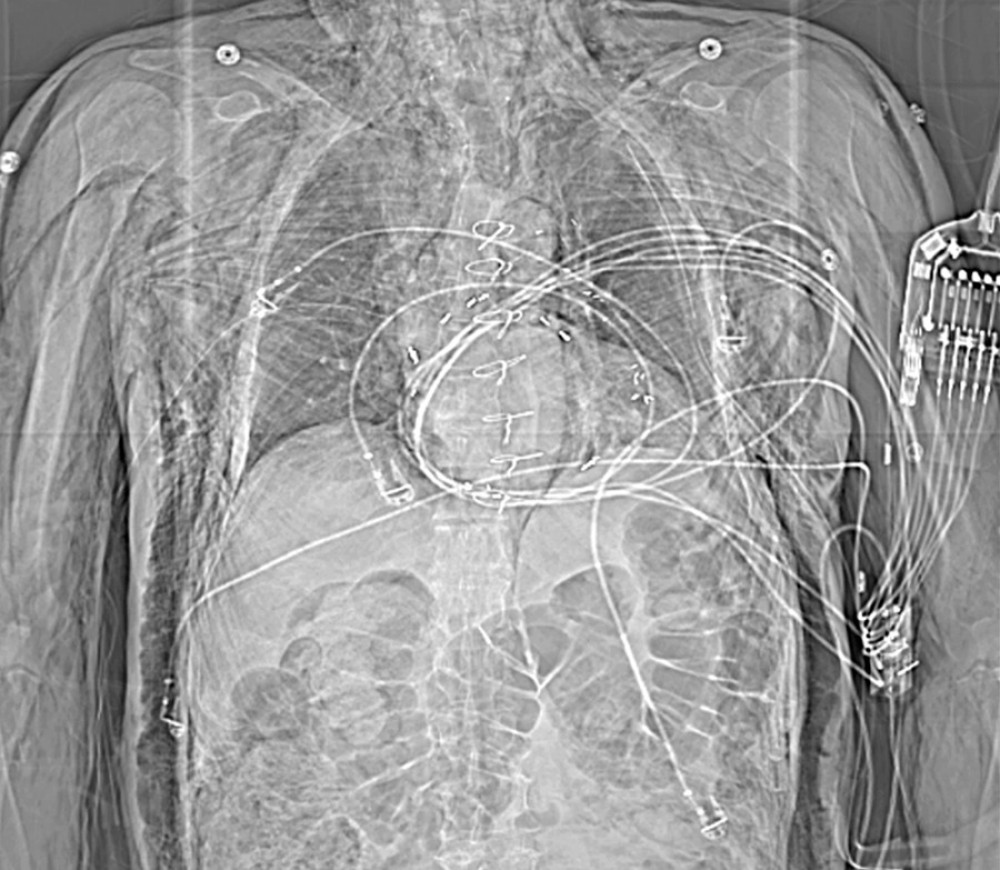

In the emergency department, he was afebrile (37°C), with a heart rate of 80 beats per minute, blood pressure 104/70 mmHg, respiratory rate of 36 breaths per minute with SpO2 of 100% while breathing 2 L/min of oxygen via nasal cannula. He was alert and oriented in mild distress. A physical exam revealed a marked crepitus from head to thigh with bilateral orbital emphysema making it difficult to visualize his left pupil. He had a regular rate and rhythm on cardiac auscultation. Palpable crepitus was appreciated throughout the anterior chest, but without Hamman’s sign or an accessory crunching sound. Respirations were non-labored with decreased breath sounds bilaterally. His scrotum was tender to palpation with a dehis-cent left scrotal wound. The scrotum was not grossly swollen and had no signs of free air or rapid expansion. Routine laboratory results were unremarkable except for mild leukocytosis of 12.2 k/mm3 (Table 1). A chest X-ray disclosed bilateral pneumothoraces, pneumomediastinum, and excessive sub-cutaneous air. Two chest tubes were placed before obtaining computed tomography (CT) of the chest, abdomen, and pelvis. Being in a small local emergency department, he was transferred to a larger regional hospital for further treatment. Upon arrival, concern for worsening of the right-sided pneumothorax prompted a repeat CT chest, abdomen, and pelvis (Figures 1–3). This study revealed that the chest tube was not communicating with the pneumothorax, which had increased in size from the previous report. He had placement of an additional chest tube. On hospital day 3, with resolution of the pneumotho-races, his chest tubes were removed and he was discharged in stable condition.